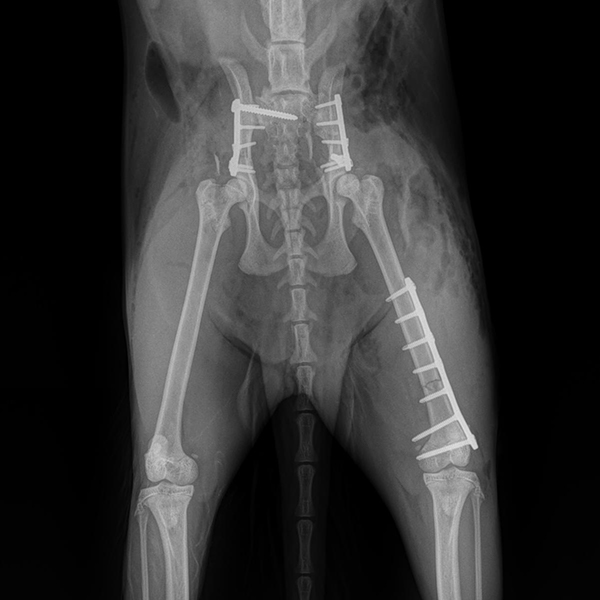

Fracture Treatment in Small Breeds:

Experience of 100 Cases

CrCL Ruptures in Small Breeds:

Osteotomies or extra capsular repair

CrCL Ruptures in Small Breeds: Should we use osteotomies instead of extra capsular repair?

TTA RAPID®

Learn how to perform CCL Repair with TTA RAPID®

Tiny TTA RAPID®

Learn how to fix CCL Ruptures in Tiny Animals with the Tiny TTA RAPID® System